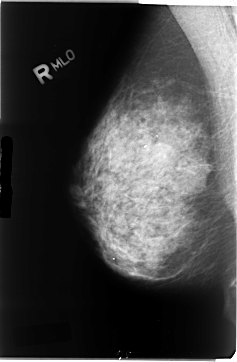

B_3044_1.RIGHT_MLO

RIGHT_CC LINES 4728 PIXELS_PER_LINE 3112 BITS_PER_PIXEL 12 RESOLUTION 50 NON_OVERLAY

RIGHT_MLO LINES 4696 PIXELS_PER_LINE 3080 BITS_PER_PIXEL 12 RESOLUTION 50 NON_OVERLAY